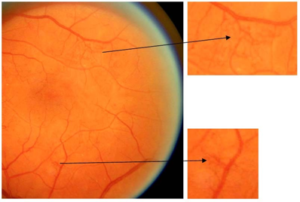

视盘的评估

与此同时,以下视神经盘的评估可帮助患者发现其他暂无症状、但有健康风险的疾病,如早期青光眼或脑肿瘤。这可能会帮助挽救患者的健康和生命。

- 视盘的边界;

- 视盘的颜色;

- 杯盘比:视杯纵轴长度和视盘纵轴长度的比值(十分位比值);

- 盘沿出血;

- 局限性视神经纤维束缺失。

▲ 视杯扩大:图中大视杯的杯盘比达到了7/10或0.7

▲ 局限性视神经纤维束缺失